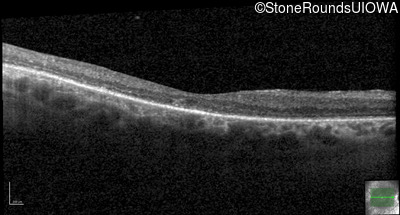

Age at visit: 59 years